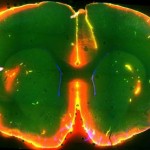

El estudio , publicado hoy en la revista Science, revela que el método único en el cerebro de la eliminación de residuos – conocido como el sistema glymphatic – es muy activa durante el sueño, quitando las toxinas responsables de la enfermedad de Alzheimer y otros trastornos neurológicos. Además, los investigadores encontraron que durante el sueño, las células del cerebro se reducen de tamaño, lo que permite los residuos a eliminar con mayor eficacia.

Los nuevos resultados de la bisagra en el descubrimiento el año pasado por Nedergaard y sus colegas de un sistema hasta ahora desconocido de la eliminación de desechos que es único en el cerebro. El sistema responsable de la eliminación de residuos celulares en el resto del cuerpo , el sistema linfático , no se extiende a la del cerebro . Esto es debido a que el cerebro mantiene su propia «ecosistema » cerrado y está protegido por un sistema complejo de puertas de enlace molecular – llamada la barrera sangre – cerebro – que controlan estrechamente lo que entra y sale del cerebro .